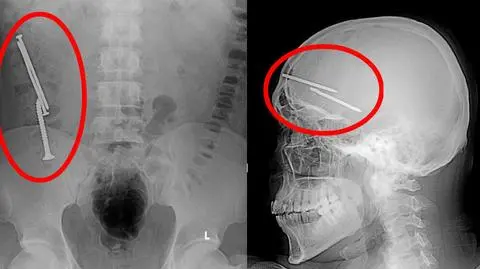

Śruba połknięta przez skazanego - zdjęcie RTG

Najpopularniejsze metody samookaleczenia to "zarzucanie na połyk" (czyli połykanie wszystkiego, co przejdzie przez przełyk) i "wbitki" (czyli wbijanie gwoździ lub śrub w głowę, oko czy okolice serca).

- Spotkałem się z przypadkiem osadzonego, który wbijał sobie gwoździe w głowę. Ich końce utkwiły pomiędzy półkulami mózgowymi więźnia. Tu też było o krok od śmierci - opowiada dr Kahlan.